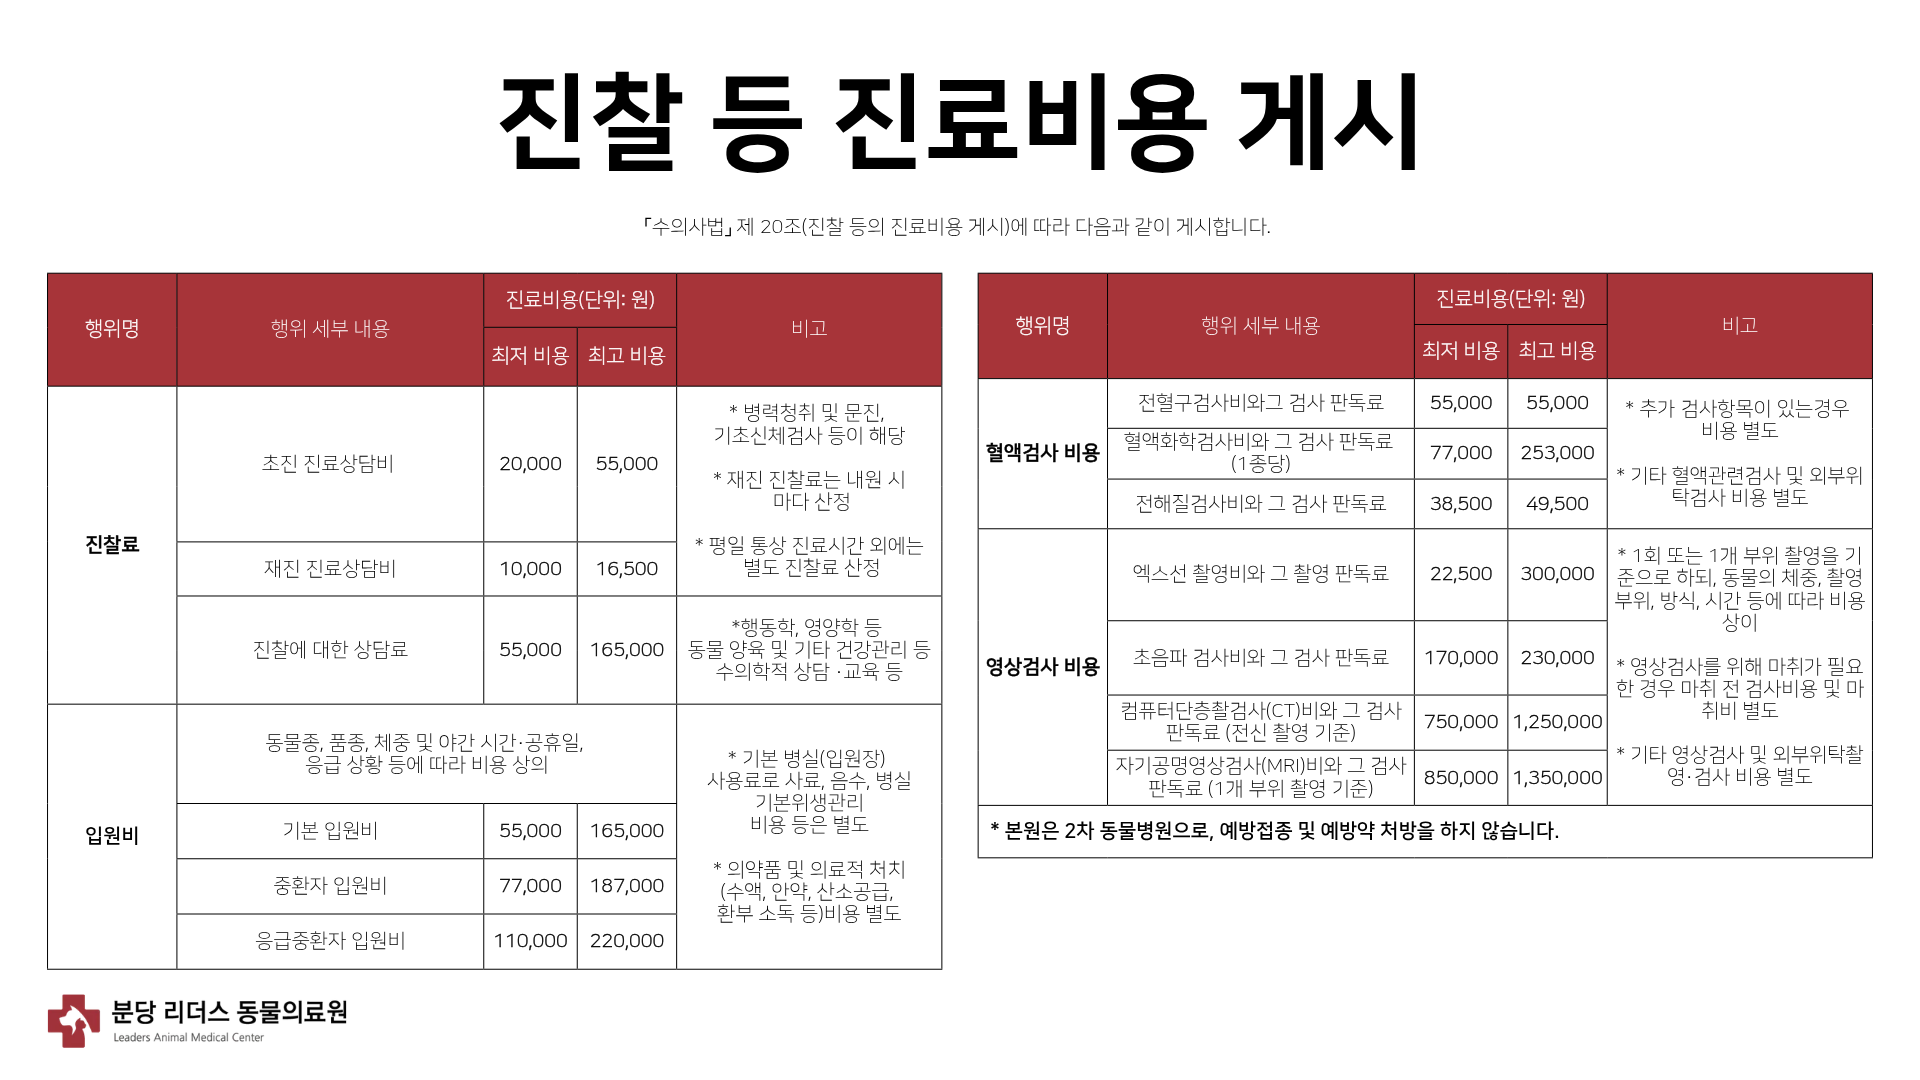

이번에 소개해드릴 환자는 10살의 중성화된 암컷 코리안숏헤어로, 최근 호흡수가 눈에 띄게 증가하고 양쪽 뒷다리를 갑자기 사용하지 못하는 증상이 발생하여 본원에 내원하였습니다. 해당 증상은 단순한 호흡기 문제나 신경 질환뿐 아니라 심장 질환과 혈전 합병증 가능성까지 함께 고려해야 하는 상황이었기 때문에, 정확한 원인 평가를 위해 방사선 검사와 심장 초음파 검사를 진행하였습니다.

방사선 검사에서 다음과 같은 소견이 확인되었습니다.

환자의 방사선검사 사진/ 출처: 24시 동탄리더스동물의료원

- 심장 실루엣이 valentine shape로 관찰되었으며, 실제 측정 결과 심장 크기 VHS 9.7v, VD short axis 5.3v로 심한 심비대가 확인되었습니다.

- 폐의 앞쪽을 따라 주행하는 폐정맥이 미약한 확장된 모습을 보였습니다.

- 양쪽 폐의 후엽에서 폐 실질 하얗게 보이는 소견(alveolar pattern)이 관찰되었습니다.

- 우측 폐 중엽과 후엽 사이 미약한 fissure line( 얇은 선 모양의 변화) 관찰되었습니다.

- 또한 식도와 위 안에 가스가 다량 차 있는 모습이 확인되었습니다.

위 소견을 종합하였을 때, 심한 심비대와 폐수종 소견이 확인되어 고양이 비대성 심근병증(HCM), 제한성 심근병증(RCM) 등을 포함한 심근병증(cardiomyopathy)가 강하게 의심되었습니다.

치료 후 방사선 사진 / 출처: 24시 동탄리더스동물의료원

치료 이후 환자는 심장 크기가 감소하였고 폐수종이 완화되었습니다. 양측 후지 마비도 점차 개선되는 경과를 보였습니다.